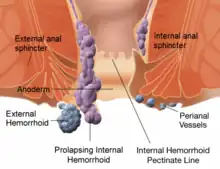

| Diagram demonstrating the anatomy of both internal and external hemorrhoids | |

Hemorrhoid cushions are important for continence. They contribute to 15–20% of anal closure pressure at rest and protect the internal and external anal sphincter muscles during the passage of stool.[8] When a person bears down, the intra-abdominal pressure grows, and hemorrhoid cushions increase in size, helping maintain anal closure.[5] Hemorrhoid symptoms are believed to result when these vascular structures slide downwards or when venous pressure is excessively increased.[11] Increased internal and external anal sphincter pressure may also be involved in hemorrhoid symptoms.[5] Two types of hemorrhoids occur: internals from the superior hemorrhoidal plexus and externals from the inferior hemorrhoidal plexus.[5] The pectinate line divides the two regions.[5]

Hemorrhoids are typically diagnosed by physical examination.[6] A visual examination of the anus and surrounding area may diagnose external or prolapsed hemorrhoids.[8] A rectal exam may be performed to detect possible rectal tumors, polyps, an enlarged prostate, or abscesses.[8] This examination may not be possible without appropriate sedation because of pain, although most internal hemorrhoids are not associated with pain.[1] Visual confirmation of internal hemorrhoids may require anoscopy, insertion of a hollow tube device with a light attached at one end.[5] The two types of hemorrhoids are external and internal. These are differentiated by their position with respect to the pectinate line.[1] Some persons may concurrently have symptomatic versions of both.[5] If pain is present, the condition is more likely to be an anal fissure or external hemorrhoid rather than internal hemorrhoid.[5]

Internal hemorrhoids originate above the pectinate line.[12] They are covered by columnar epithelium, which lacks pain receptors.[2] They were classified in 1985 into four grades based on the degree of prolapse:[1][2]

External hemorrhoids occur below the dentate (or pectinate) line.[12] They are covered proximally by anoderm and distally by skin, both of which are sensitive to pain and temperature.[2]